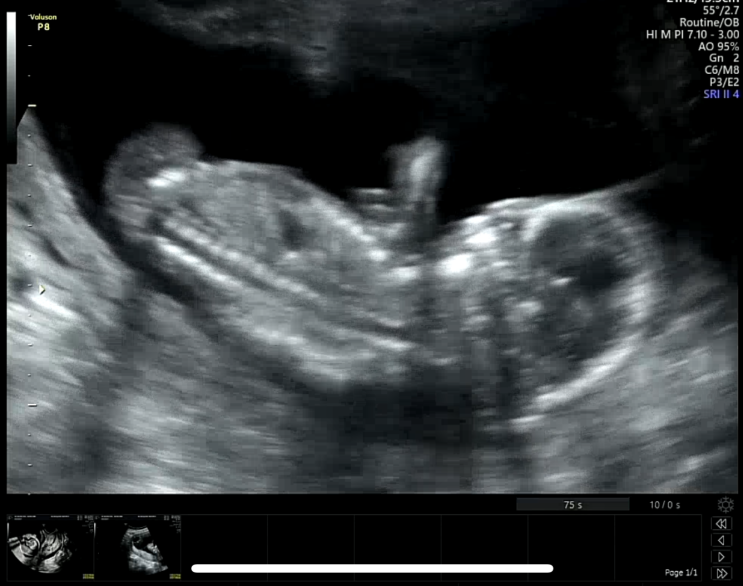

18주:: 임신중기 배통증및 배뭉침 수축검사

요근래 스트레스가 많았어서 그런지 배가 뭉치는 증상이 좀 심하다고 느꼈어요 (몸 통증에 꽤나 예민한편.....